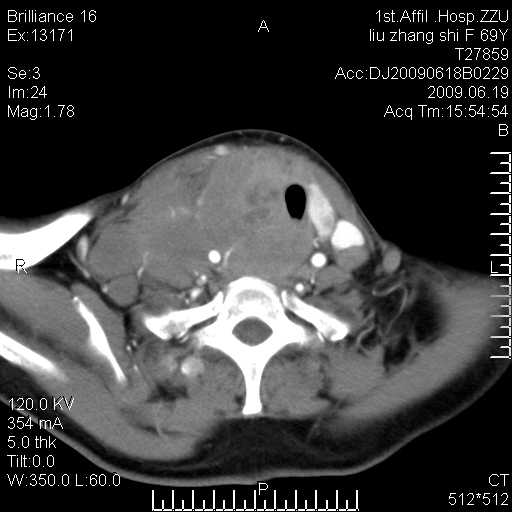

标题: CT26782:女,69岁,颈部占位,3天后公布病理结果。

【病理证实系列】女,69岁,颈部占位,有病理结果,3天后公布。(由于病例时间较久,临床资料不全,请网友见谅)本系列将有几百种常见、少见及罕见病例,均经病理证实。病例资料来自郑州大学第一附属医院。与网友共享,本人有空就发。

甲状腺癌并颈部淋巴结转移。感谢楼主的良苦用心,谢谢。

甲状腺癌并颈部淋巴结转移。

需与鼻咽癌鉴别!

支持甲状腺癌广泛侵及周围结构并颈部淋巴结转移。

鉴别:淋巴瘤、恶性神经源性病变、恶性纤维组织细胞瘤。

病理结果:颈部非霍奇金淋巴瘤。

右侧甲状腺确实有问题